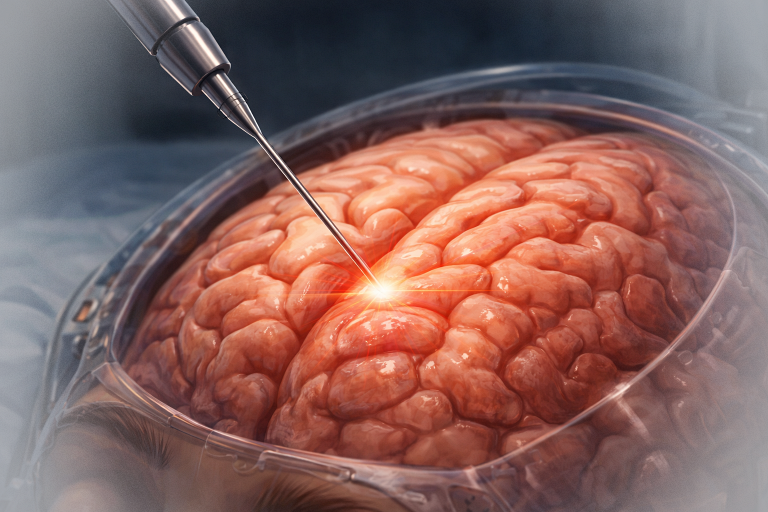

- Biopsie cerebrală stereotactică – esențială pentru diagnostic histologic.

- Chirurgia – limfoamele cerebrale sunt una dintre puținele tumori cerebrale care nu se operează. Fiind vorba de o tumoră generată de celule extrem de mobile, din sistemul imunitar, ele recidivează foarte repede chiar în condițiile unei rezecții complete. Singura formă de operație în cazul lor este biopsia cerebrală, care are doar rol diagnostic, nu curativ. Excepțional, în cazul unor tumori de mari dimensiuni, se poate lua decizia unei rezecții tumorale cu scopul de a reduce presiunea intracraniană.